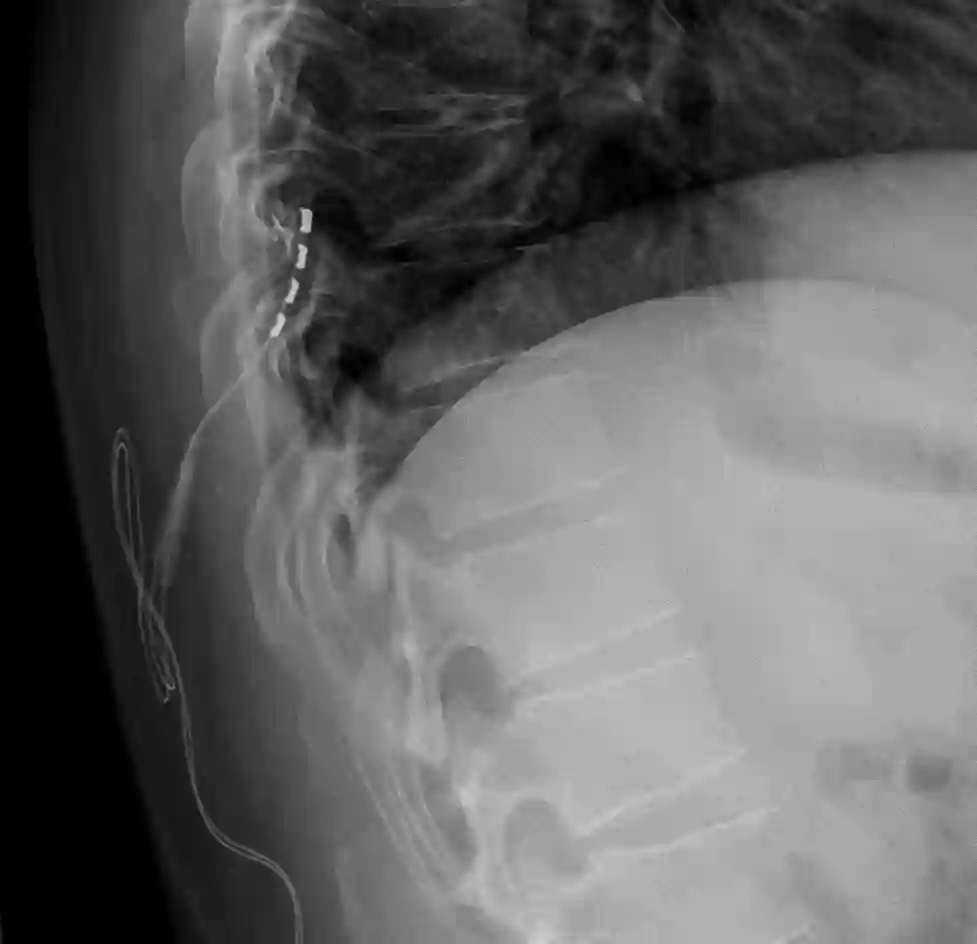

Stabelektrode

Stabelektrode im Röntgen

Darstellung von zwei Stabelektroden zur Rückenmarksstimulation im ap Röntgenbild.